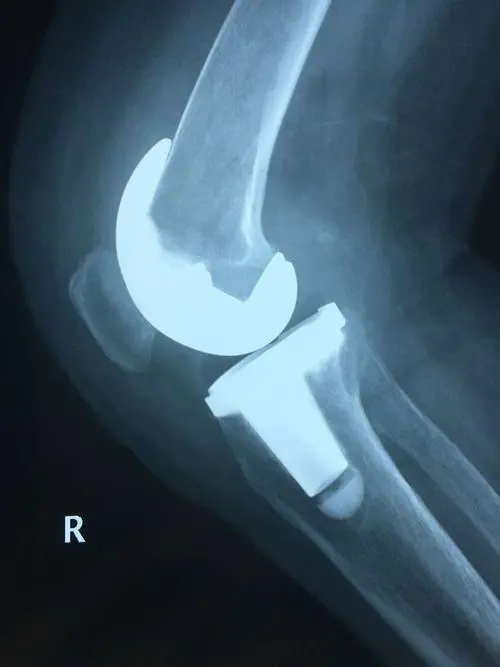

布骨医学科普:做完关节置换术后可以运动吗?这里有你要的答案!

布骨康复医疗中心 ,2021-04-12

很多做过膝关节置换术的患者都有这样的疑问,我术后可以正常走路吗?可以运动吗?走多少路合适呢?走路或者运动会不会影响我假体的寿命呢?今天给大家从业内顶级期刊《Journal of Bone & Joint Surgery-American Volume》说说膝关节置换术后的患者朋友们经常遇到的一些问题.....